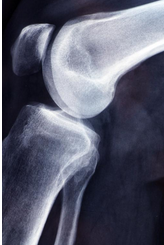

무릎 연골 손상 증상에 대해 제대로 살펴보도록 하겠습니다.무릎 연골은 무릎 관절의 부드러운 조직으로, 무릎 관절을 지키고 스트레스를 흡수하는 역할을 합니다. 연골은 거의 모든 물과 콜라겐 섬유로 이루어져 있으며, 신체 내부의 혈관이나 신경이 없기 때문에 손상된 경우 치료가 어려울 수 있습니다. 연령이 들면서 연골의 수명이 줄어들 수 있고, 부상이나 연골의 낭비에 따라 연골이 파손되거나 마모될 수 있습니다. 이와 같은 상황에서는 통증, 불안정감 및 관절 운동 제한 등의 증상이 발생할 수 있습니다. 적절한 치료를 받지 않으면 무릎 관절염과 같은 더 큰 문제가 발생할 수 있으므로, 빠르게 진단하고 적절한 치료 계획을 수립하는 것이 중요합니다.

무릎 연골 손상 증상

무릎 연골 손상의 증상은 아래와 같습니다.